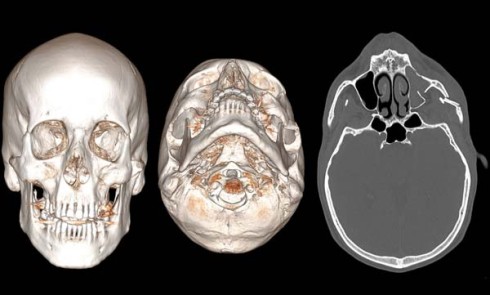

Article réservé à nos abonnés À propos d’un traumatisme facial

Un homme âgé de 45 ans se présente à la consultation de stomatologie et de chirurgie maxillo-faciale à la suite...